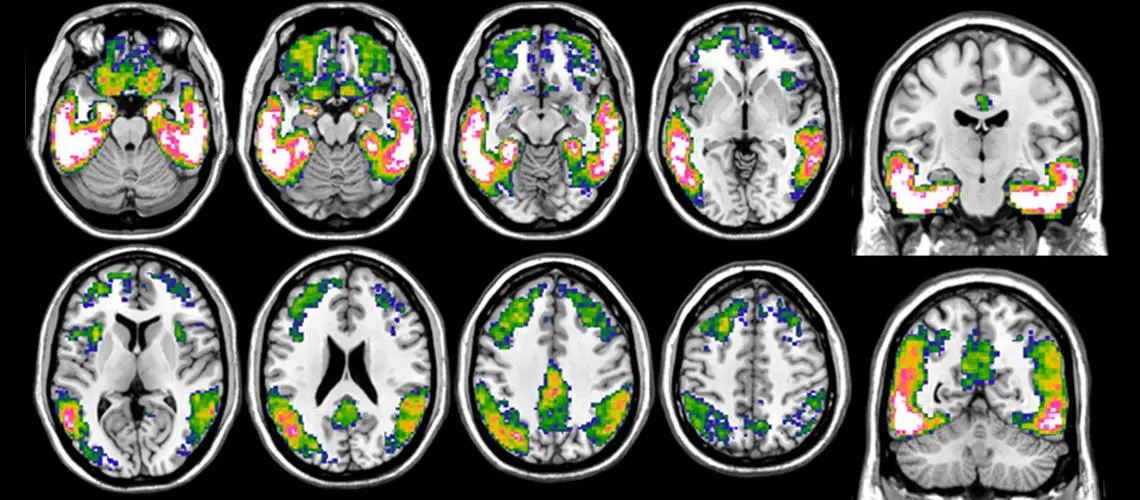

用 18F-Flortaucipir PET 对阿尔茨海默氏症中的 Tau 进行成像。图中显示的是通过比较阿尔茨海默病患者与健康对照组的 tau 负荷而得出的典型 tau 累积模式。从蓝色到白色的色标表示更明显的tau负荷,粉白色区域代表最高的积累。资料来源:UNIGE

Flortaucipir是一种能与tau蛋白结合的放射性示踪剂。它由一家制药公司开发,并于2020年获得美国食品药品管理局(FDA)批准。它可以检测 tau 蛋白的积累及其在大脑中的分布,从而精确评估其在疾病临床表现中的作用。